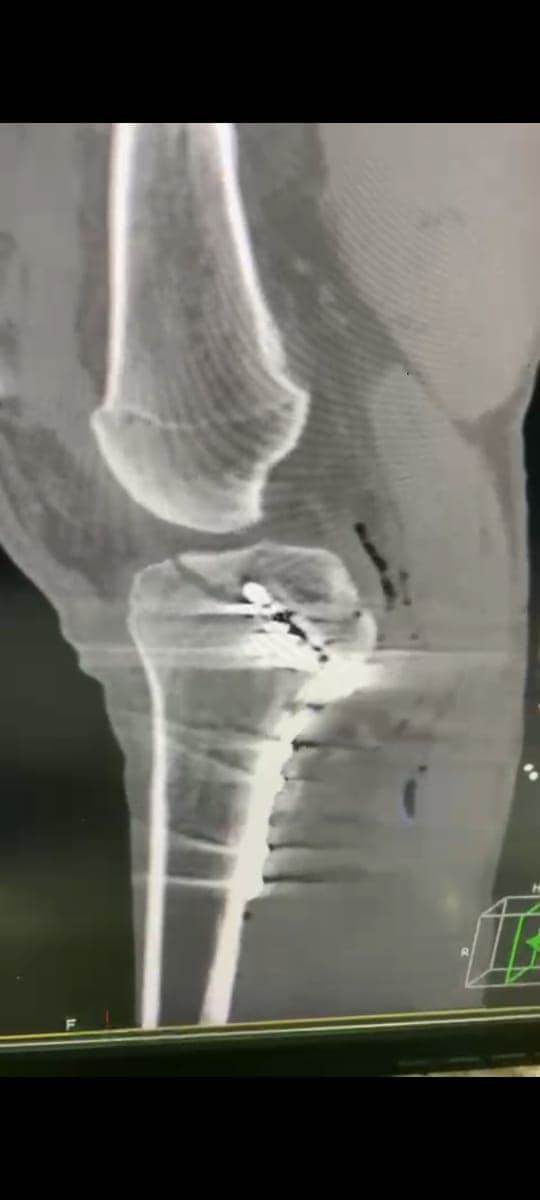

مشيرًا الى أن ذلك النوع من الكسور يكون قريبًا جدًا من الأعصاب والأوعية الدموية الرئيسية للساق والتي توجد خلف مفصل الركبة.. حيث تم الوصول الى الكسر وإعادة بناء سطح المفصل وتثبيته باستخدام شريحة ومسامير وأسلاك معدنية باستخدام جرح ٧ سنتيمترات خلف الركبة واستخدام مسامير جانبية مجوفة بدون فتح لتثبيت الجزء الخارجى من سطح المفصل، وتم الاطمئنان على الأوعية الدموية قبل إفاقة المريض، وبعد تمام الإفاقة.. تم الاطمئنان على الأعصاب والأوعية للمريض.

وأضاف أنه نظرًا لقرب هذا الكسر من سطح المفصل تم عمل أشعة مقطعية بعد الجراحة للتأكد من جودة بناء المفصل وعدم وجود أى بروز للمسامير داخل المفصل، وجارٍ تحضير المريض لعمل رنين مغناطيسى لتحديد الأربطة الداخلية والخارجية للركبة التي ستحتاج لإعادة بناء بالمنظار.